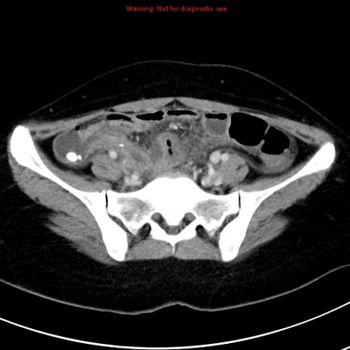

A 17-year-old male patient, no past medical history, presented with two-month history of left groin swelling with gradual increase in size and now pain.